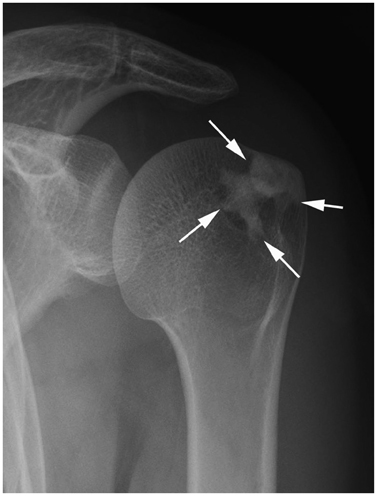

Systematic Approach of Sclerotic Bone Lesions Basis on Imaging Findings

- Sclerotic bone lesions are common, but there are diverse groups of tumors and non-tumorous lesions. Although plain radiograph and computed tomography can reveal important characteristics of these lesions, diagnosis is often challenging for radiologists. A systematic approach and familiarity with the imaging features of various sclerotic bone lesions may be greatly helpful for eliminating in the differential diagnosis. This review describes the systematic approach to diagnosing sclerotic bone lesions based on imaging findings.